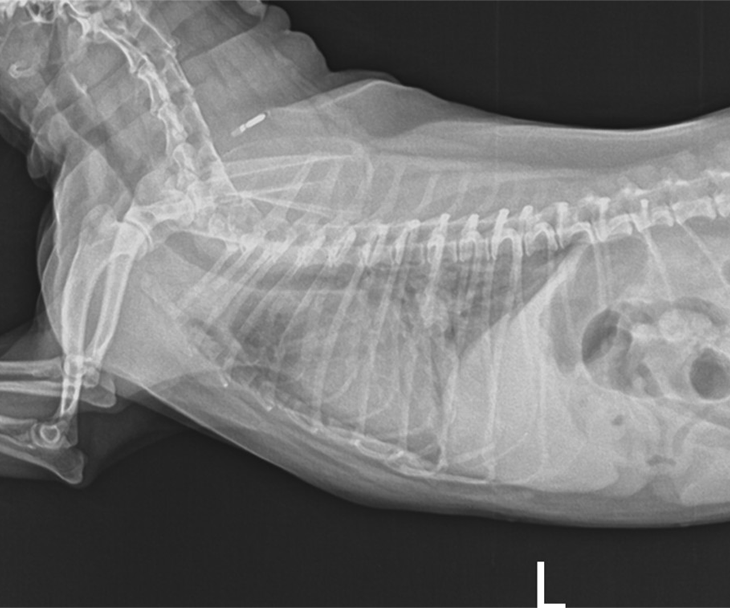

동맥관 개존증

동맥관 개존증은 선천성 심장병으로, 출생 후에도 동맥관이 올바르게 닫히지 않고 열려 있는 상태를 지칭합니다. 이러한 상태는 혈류에 이상을 초래할 수 있으므로 보통 6개월 이내에 개입해야 합니다. 외과적 수술뿐만 아니라 중재적 시술(ACDO등의 이식물 삽입 등)로도 비교적 간단하게 치료할 수 있습 니다. 심장 초음파 검사를 통해 형태와 크기를 평가한 후시술 방법을 결정하게 됩니다. 이러한 중재적 시술은 수술에 비해 통증이 적고 입원 기간이 짧아 환자의 부담을 최소화할 수 있습니다.